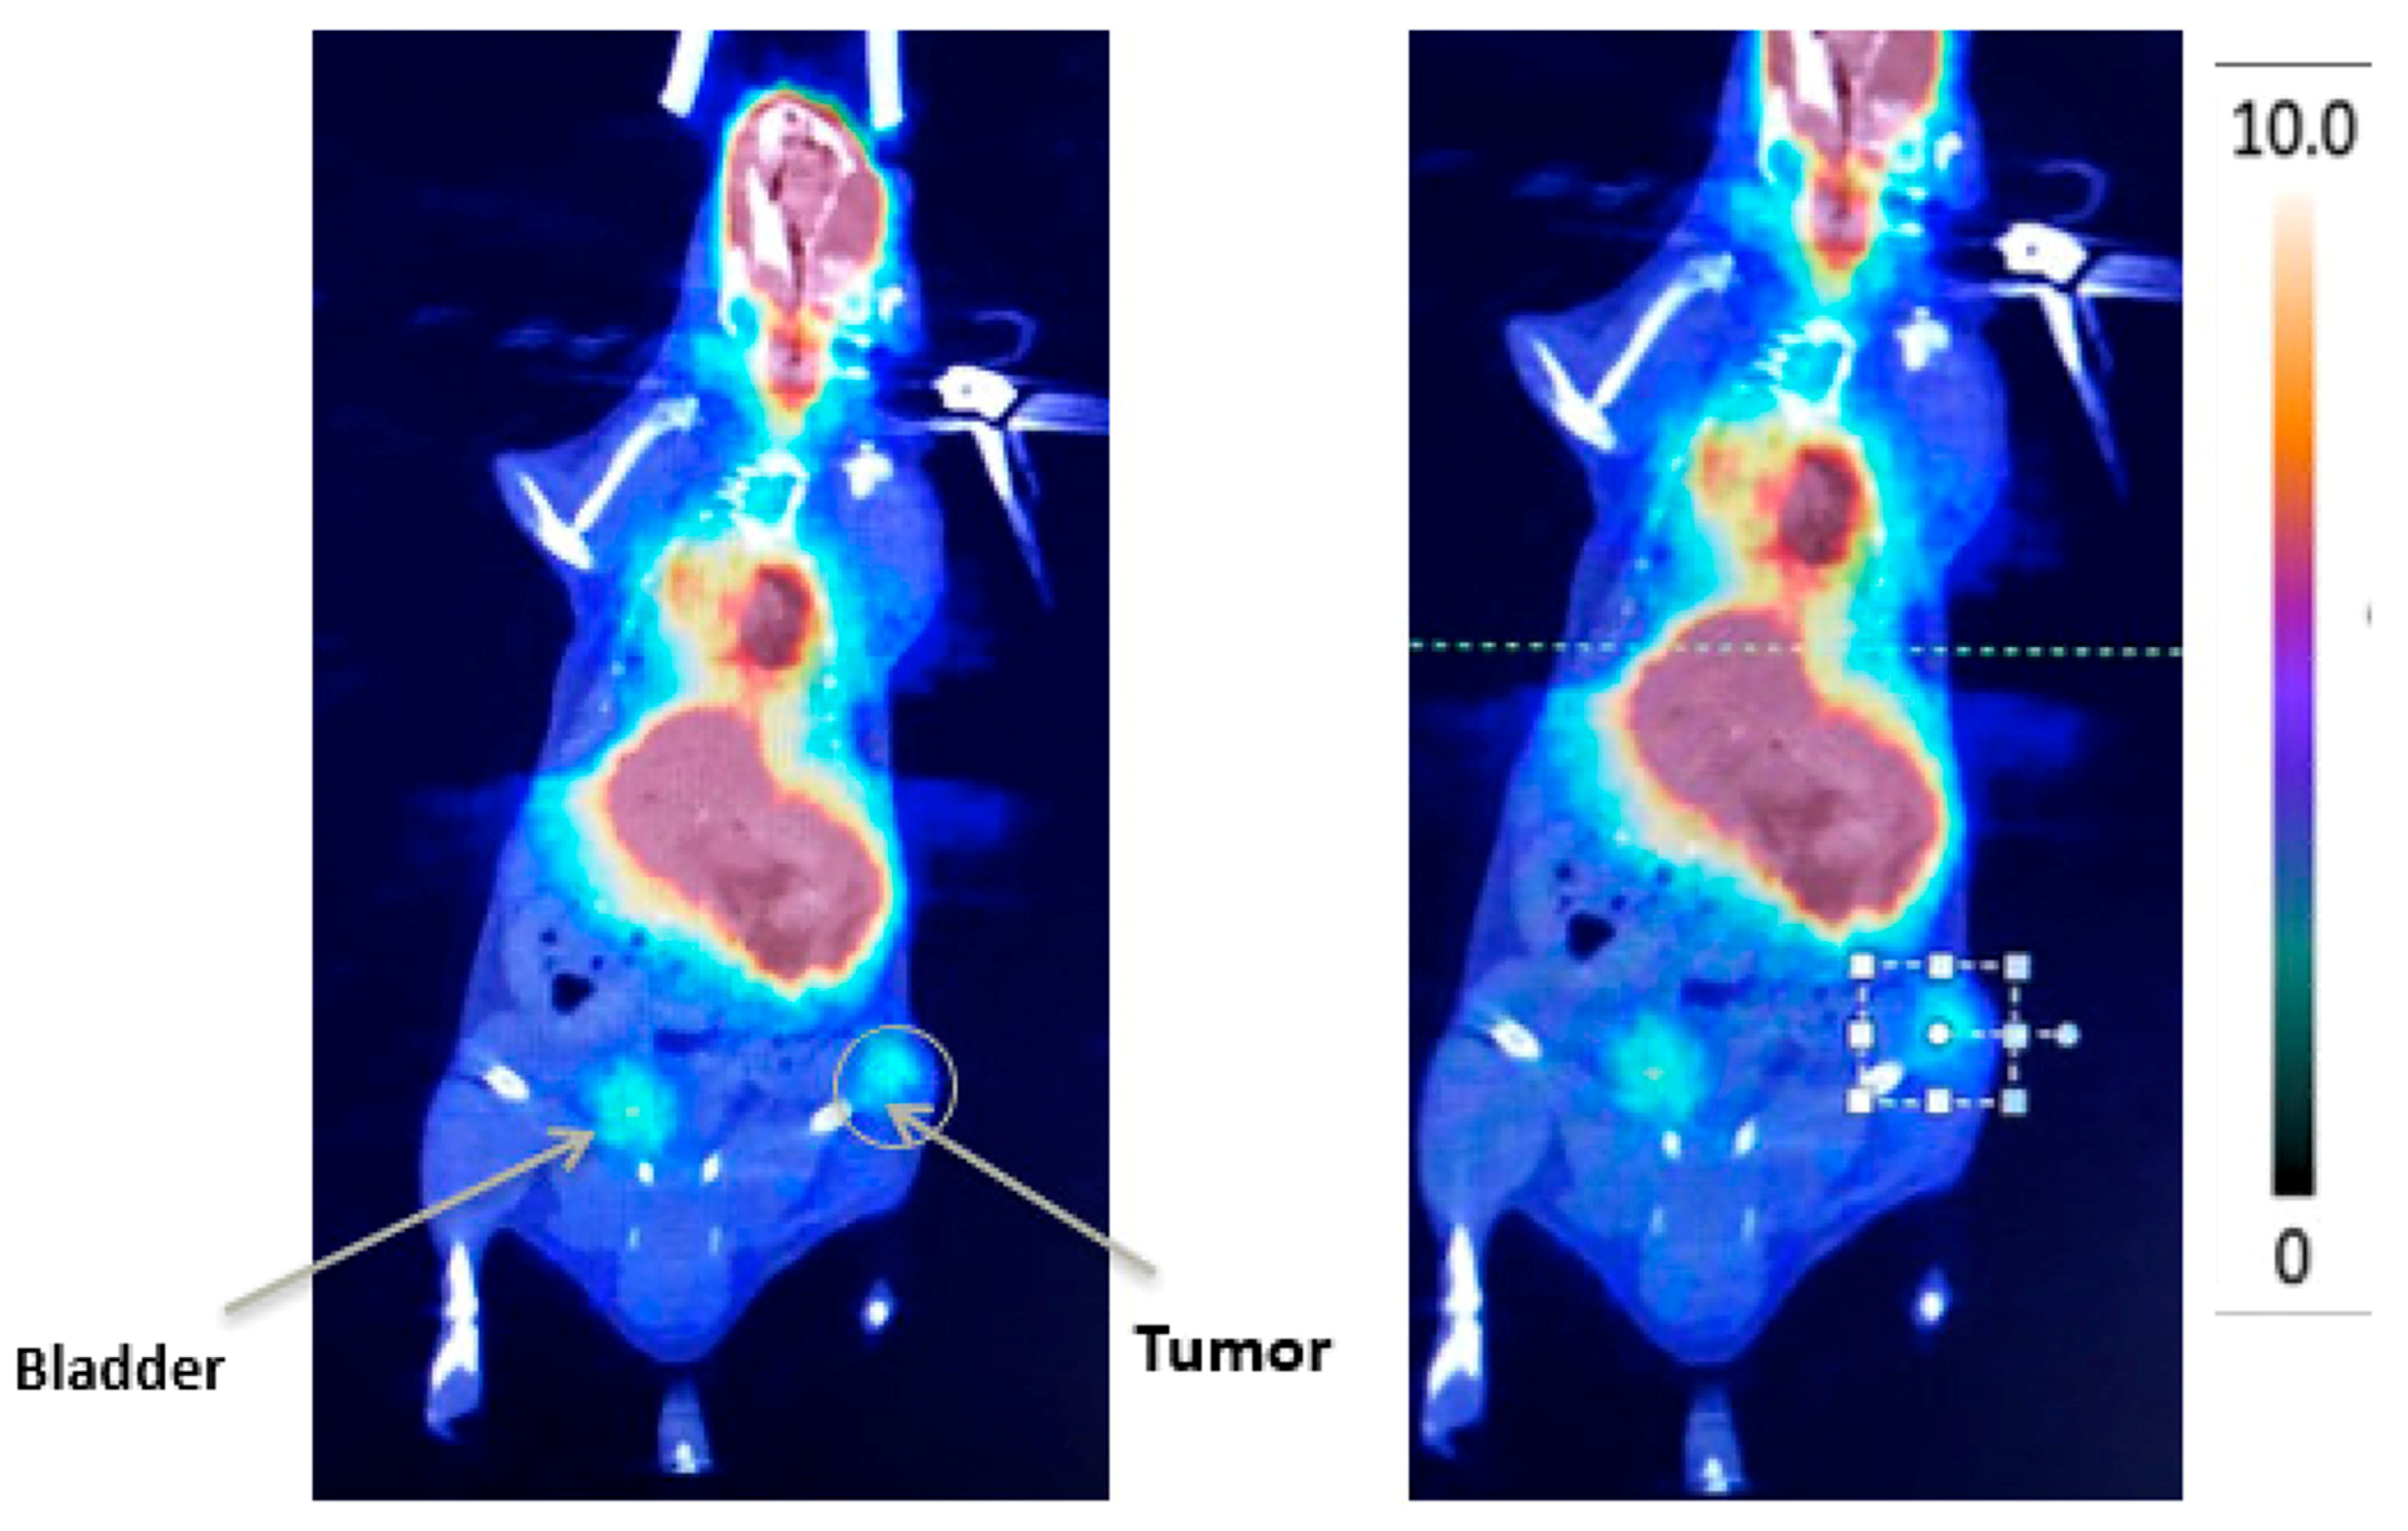

- Alvim, R.; Nagar, K.; Das, S.; Lebdai, S.; Wong, N.; Somma, A.; Hughes, C.; Thomas, J.; Monette, S.; Scherz, A.; et al. Positron Emission Tomography/Computed Tomography with Gallium-68-labeled Prostate-specific Membrane Antigen Detects Relapse After Vascular-targeted Photodynamic Therapy in a Prostate Cancer Model. Eur. Urol. Focus 2019. [Google Scholar] [CrossRef] [PubMed]

- Kim, K.; Zhang, H.; La Rosa, S.; Jebiwott, S.; Desai, P.; Kimm, S.; Scherz, A.; O’Donoghue, J.A.; Weber, W.A.; Coleman, J. Bombesin Antagonist-Based Radiotherapy of Prostate Cancer Combined with WST-11 Vascular Targeted Photodynamic Therapy. Clin. Cancer Res. 2017, 23, 3343–3351. [Google Scholar] [CrossRef] [PubMed] [Green Version]